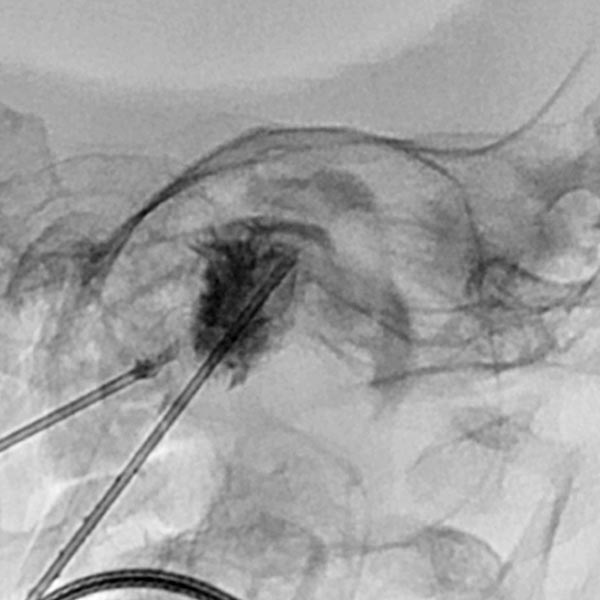

In view of the hypervascularization and the extension into the orbit, a preoperative embolization was performed with ethylene-vinyl alcohol copolymer in a direct puncture technique. Intraoperative DSA with venous drainage is depicted here.

The X-ray fluoroscopy image shows the embolic agent within the vessels in black (radiopaque). The perfusion of the infantile hemangioma was super-selectively reduced.